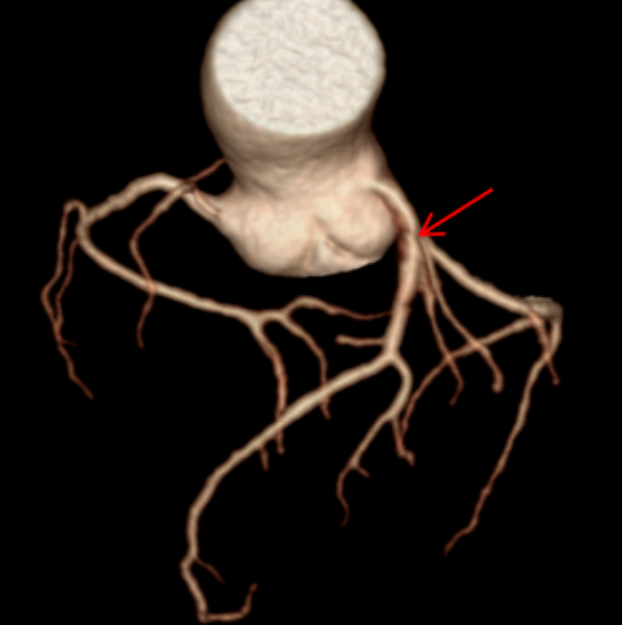

CT表现:冠状动脉粥样硬化,左冠状动脉前降支近端中度狭窄,左冠状动脉前降支心肌桥形成。

正常情况下,血管走在心脏表面,收缩舒张自由;而当血管被心肌“桥”覆盖时,心脏每次收缩挤压,都可能短暂压迫这段血管,影响远端的血液供应。狭窄加上心肌桥的叠加效应,很好地解释了他为何出现胸闷、胸痛(心绞痛)和心律不齐的症状——心肌正在发出“缺血”的求救信号。

冠状动脉CTA已成为筛查和诊断冠状动脉疾病的无创性“金标准”之一。它通过静脉注射对比剂,利用CT快速多层扫描和三维重建技术,直观展示冠状动脉的走行、管腔狭窄程度、斑块性质(如钙化斑块或软斑块)以及血管壁的情况。对于像张老先生这样的病例,CTA不仅能精准测量狭窄百分比,还能识别心肌桥这一解剖变异,评估其与狭窄的相互影响,为临床制定治疗方案(是药物保守治疗,还是需要介入支架或外科搭桥)提供了至关重要的参考。报告中提到的宽体探测器技术,代表了当前CT发展的前沿方向,特别适用于心率快、心律不齐、不能配合屏气或身体虚弱的患者,极大地拓宽了心脏CT检查的适用人群和诊断成功率。